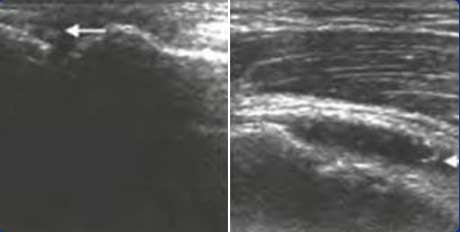

������ʴ

��ֺ�ؽڹ��ʱ���IJ�������Ϊ������ʴ

����֯����

���ؽ��ڲ����������ȣ�ʹ������Χ����֯��ԵǷ����